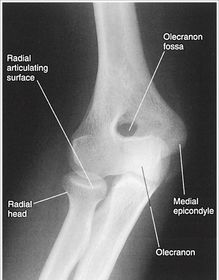

| AP Elbow | ANATOMY: distal humerus - proximal forearm CRITERIA: slight superimposition of proximal radius/ulna humeral epicondyles in profile open joint space POSITIONING: CR perpendicular @ midelbow |

| Medial Oblique Elbow | ANATOMY: proximal radius/ulna, distal humerus, medial epicondyle and trochlea CRITERIA: coronoid process in profile radial head and neck should superimpose the ulna olecranon process seen within olecranon fossa POSITIONING: CR perpendicular @ midelbow |

| Lateral Oblique Elbow | ANATOMY: open joint space, radial head, neck, tuberosity, and capitulum CRITERIA: radial head, neck, and tuberosity are free of superimposition humeral epicondyles and capitulum in profile POSITIONING: CR perpendicular @ midelbow |

| Lateral Elbow Evaluation Criteria | ANATOMY: distal humerus, proximal forearm, entire elbow joint CRITERIA: humeral epicondyles are superimposed radial tuberosity is invisible (if visible the hand is pronated) half of the radial head superimposed by coronoid process Elbow is flexed 90 degrees to see/not see fad pads 3 concentric arcs visible POSITIONING: CR perpendicular @ lateral epicondyle |